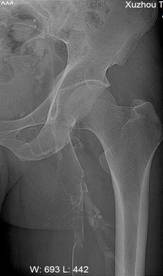

何××,男,6岁,儿童股骨头坏死,左侧股骨头骨骺坏死、骨质碎裂(图3),经治疗后骨骺骨质恢复(图4)。

图3 图4